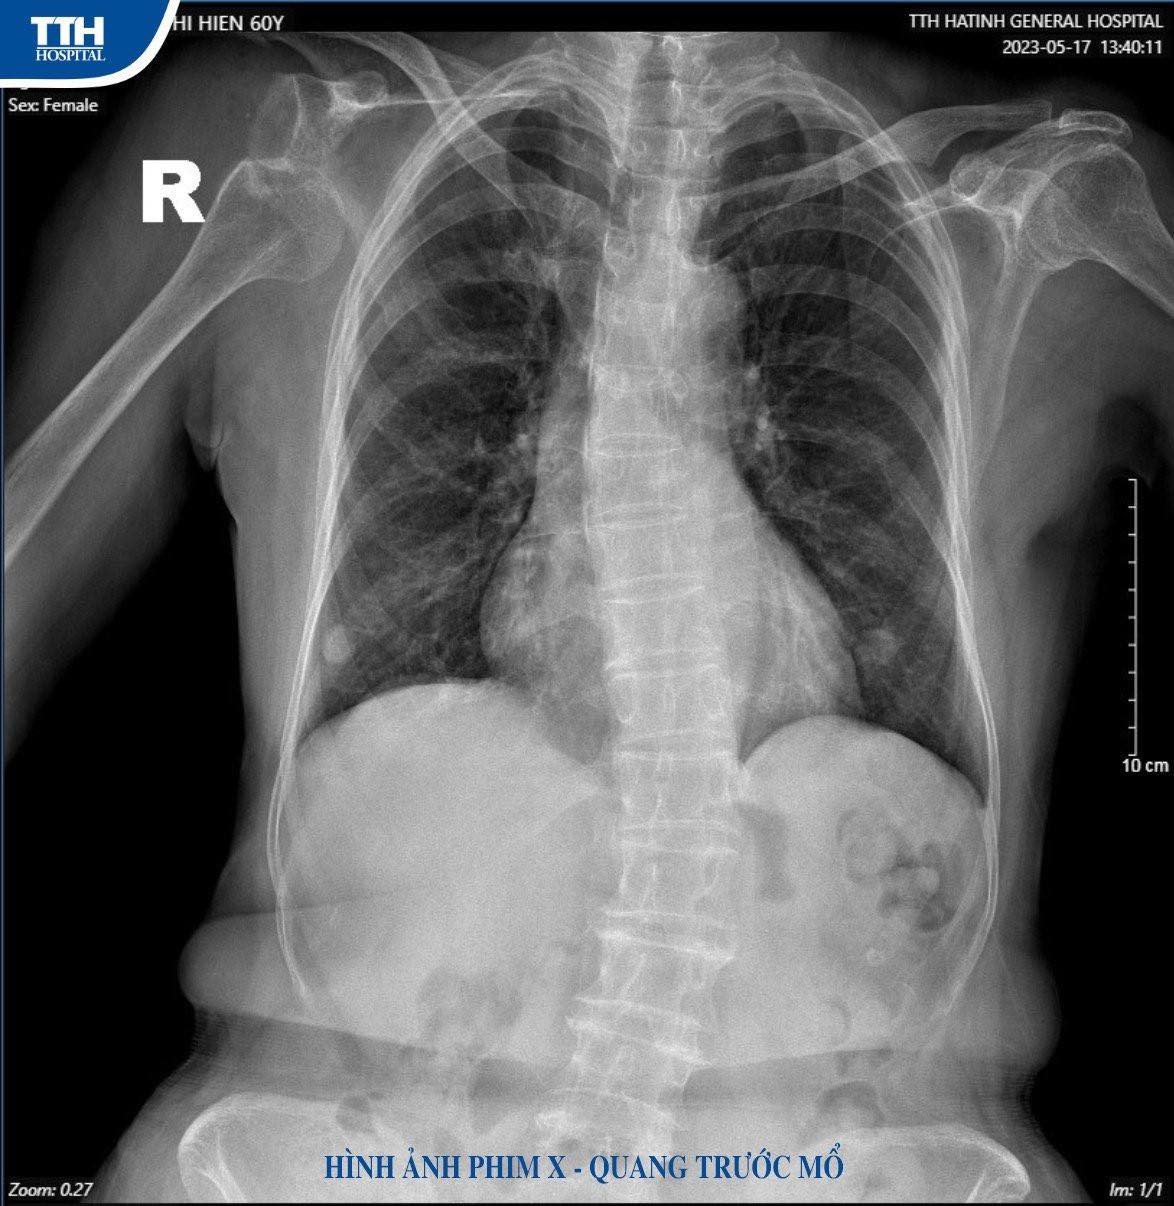

Cách đây 3 tháng, bệnh nhân N. T. H (60 tuổi) trú tại xã Tân Lâm Hương, huyện Thạch Hà, (Hà Tĩnh) bị chấn thương trật khớp vai phải do tai nạn giao thông, đã mổ nội soi tại bệnh viện tuyến trên. Tuy nhiên, sau mổ đến nay bệnh nhân vẫn xuất hiện trật khớp vai 2 lần nên nhập viện Khoa Chấn thương và Y học thể thao, Bệnh viện Đa khoa TTH Hà Tĩnh để điều trị.

Sau khi thăm khám và thực hiện các chỉ định cận lâm sàng, qua hình ảnh chụp MRI các bác sĩ chẩn đoán bệnh nhân bị trật khớp vai tái diễn, tổn thương chỏm xương, kèm tổn thương ổ chảo xương cánh tay và vỡ mấu động lớn vai phải cần tiến hành phẫu thuật bằng phương pháp Latarjet.